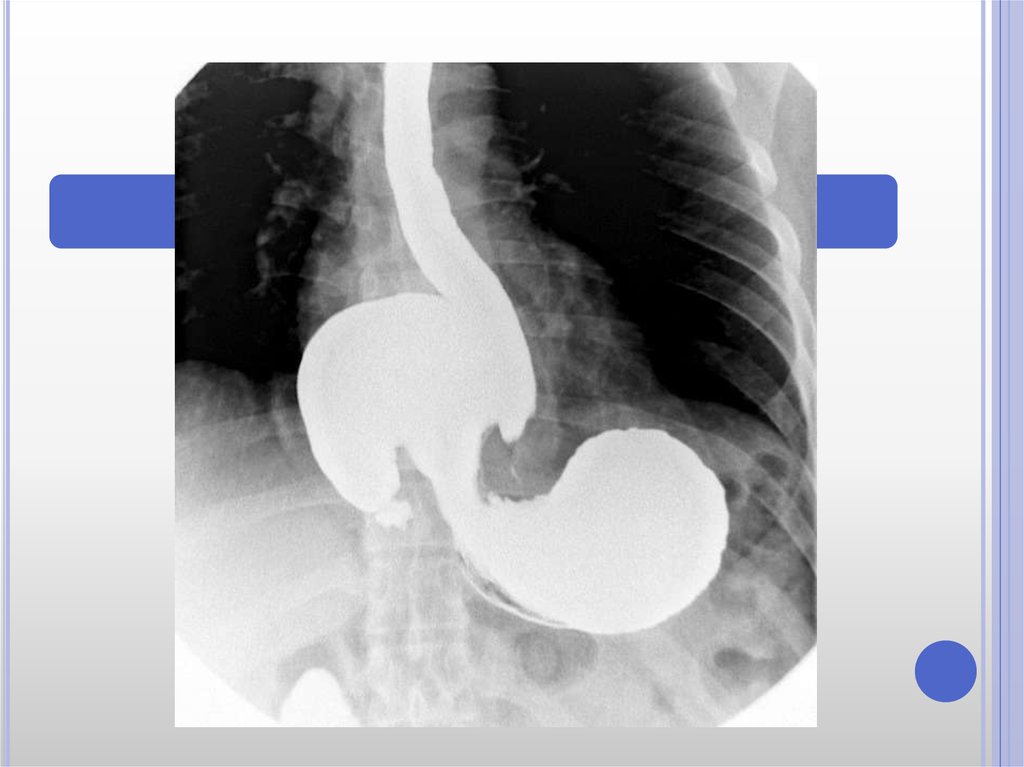

Рентгеноконтрастные Исследования Кишечника: Визуализация и Методики

Раздел: Иллюстрированный журнал